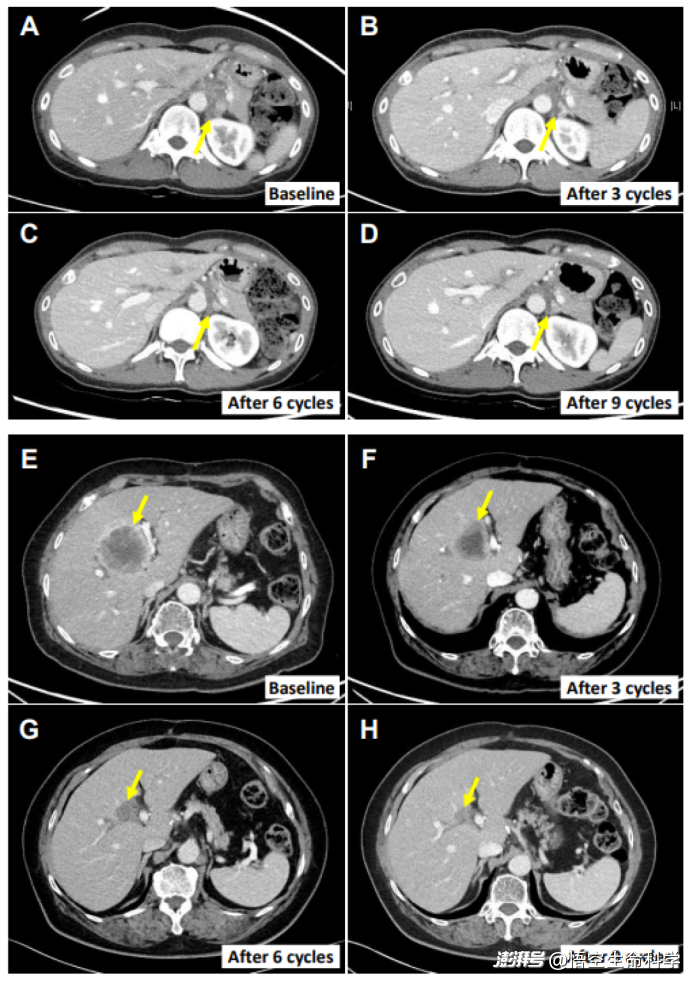

▲兩例患者的腫瘤消退情況

雖然聯(lián)合治療并未完全消除所有腫瘤,但效果遠(yuǎn)超單一的派姆單抗治療。更重要的是,患者的生存質(zhì)量得到了顯著改善,治療過(guò)程中的安全性也得到了充分保障。